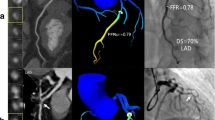

To evaluate the impact of an iterative reconstruction (IR) algorithm (advanced modeled iterative reconstruction, ADMIRE) on machine learning-based coronary computed tomography angiography–derived fractional flow reserve (CT-FFRML) measurements compared with filtered back projection (FBP). 170 plaque-containing vessels in 107 patients were included. CT-FFRML values were measured and compared among 5 imaging reconstruction algorithms (FBP and ADMIRE at strength levels of 1, 2, 3 and 5). The plaques were classified as, ‘calcified” or “noncalcified” and “≥ 50% stenosis” or “< 50% stenosis’, a total of four subgroups by consensus. There were no significant differences of CT-FFRML values among the FBP and ADMIRE 1, 2, 3 and 5 groups wherever comparisons were done at the level of subgroups (P = 0.676, 0.414, 0.849, 0.873, respectively) or overall (P = 0.072). There were 20, 21, 19, 19 and 29 vessels with lesion-specific ischemia (CT-FFRML ≤ 0.80) in FBP and ADMIRE 1, 2, 3 and 5 datasets, respectively, but no statistical differences were found (P = 0.437). Compared with CT-FFRML value of FBP dataset, the CT-FFRML values of 9 (5.3%) vessels from 8 patients (7.5%) in ADMIRE5 dataset switched from above 0.8 to below or equal to 0.8. There were no significant differences of the CT-FFRML values among the FBP and IR image algorithms at different strength levels. However, high iterative strength level (ADMIRE 5) was not recommended, which might have an impact on diagnosis of lesion-specific ischemia, although changes only occurred in a modest number of subjects.